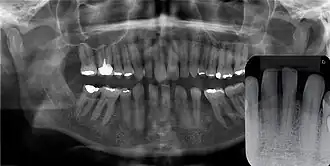

O cisto gengival tende a não ser visível em radiografias por sua origem ser exclusivamente de tecidos moles, mas em raros casos, seu crescimento pode gerar uma sombra radiolúcida ao causar a erosão óssea, e em alguns casos pode até mesmo se assemelhar ao cisto periodontal lateral pelo aspecto radiolúcido bem delimitado.[2]